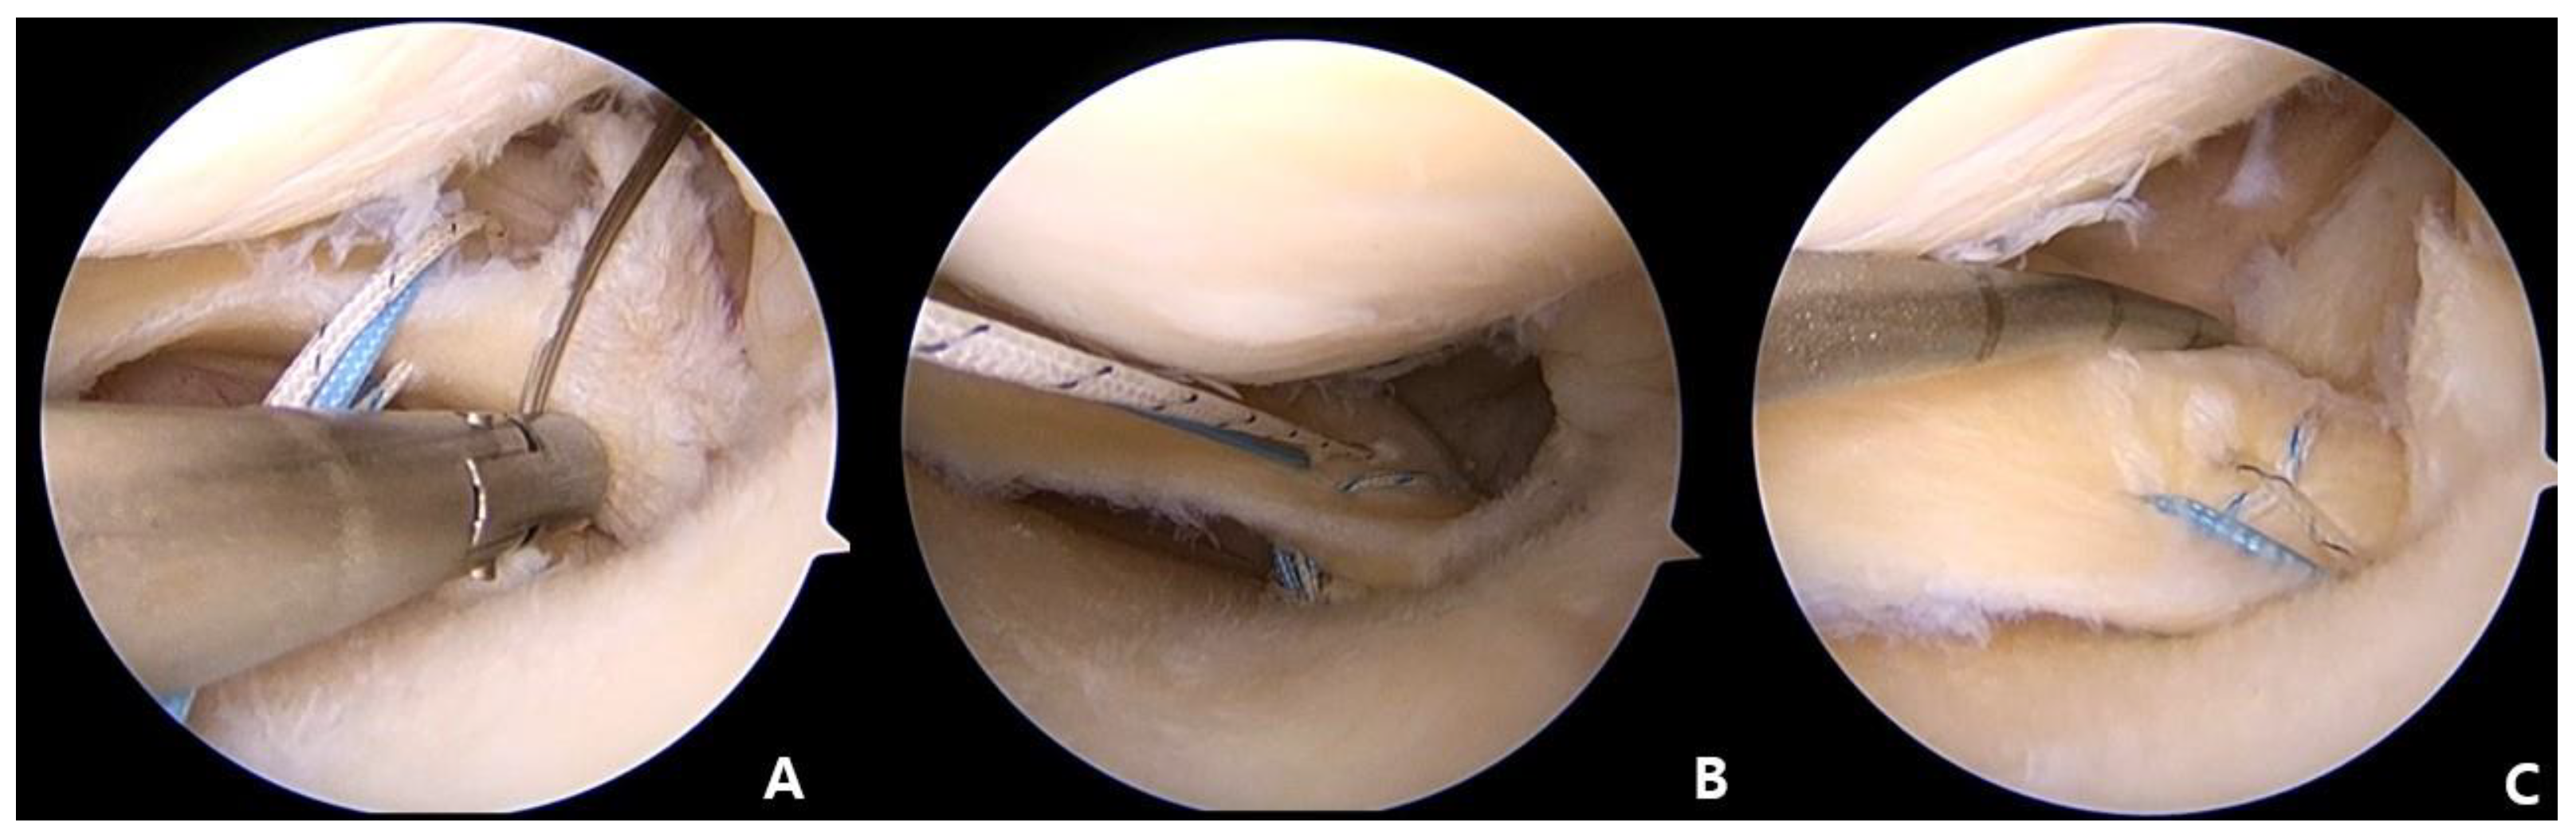

2.4. MMPR Stitches

Passage of the Knee Scorpion suture passer (Arthrex, Naples, FL, USA) loaded with a No. 2 Ultrabraid (Smith and Nephew, Andover, MA, USA) through the AM portal was then performed. The separated segment of the medial meniscus posterior horn (MMPH) was penetrated using a Scorpion needle at about 5 mm medial point to a detached margin. The second stitch was penetrated in the anterior location of the first stitch, using the same method. The upper two strands of the stitches were pulled out and tied. Using the shuttle relay technique, the first stitch was exchanged with the second stitch to make a horizontal loop (Figure 3).

The Knee Scorpion suture passer (Arthrex, Naples, FL, USA) was reintroduced using the AM portal, and two vertical stitches penetrated just the medial side of the horizontal stitch.

Figure 3. (A) The MMPH penetrated using a Knee Scorpion suture passer (Arthrex, Naples, FL, USA) at about 5 mm medial to the detached margin. (B) The second stitch located in the anterior position of the first stitch in the same manner. (C) Using the shuttle relay method, exchange of the first suture with the second suture to create a horizontal loop.